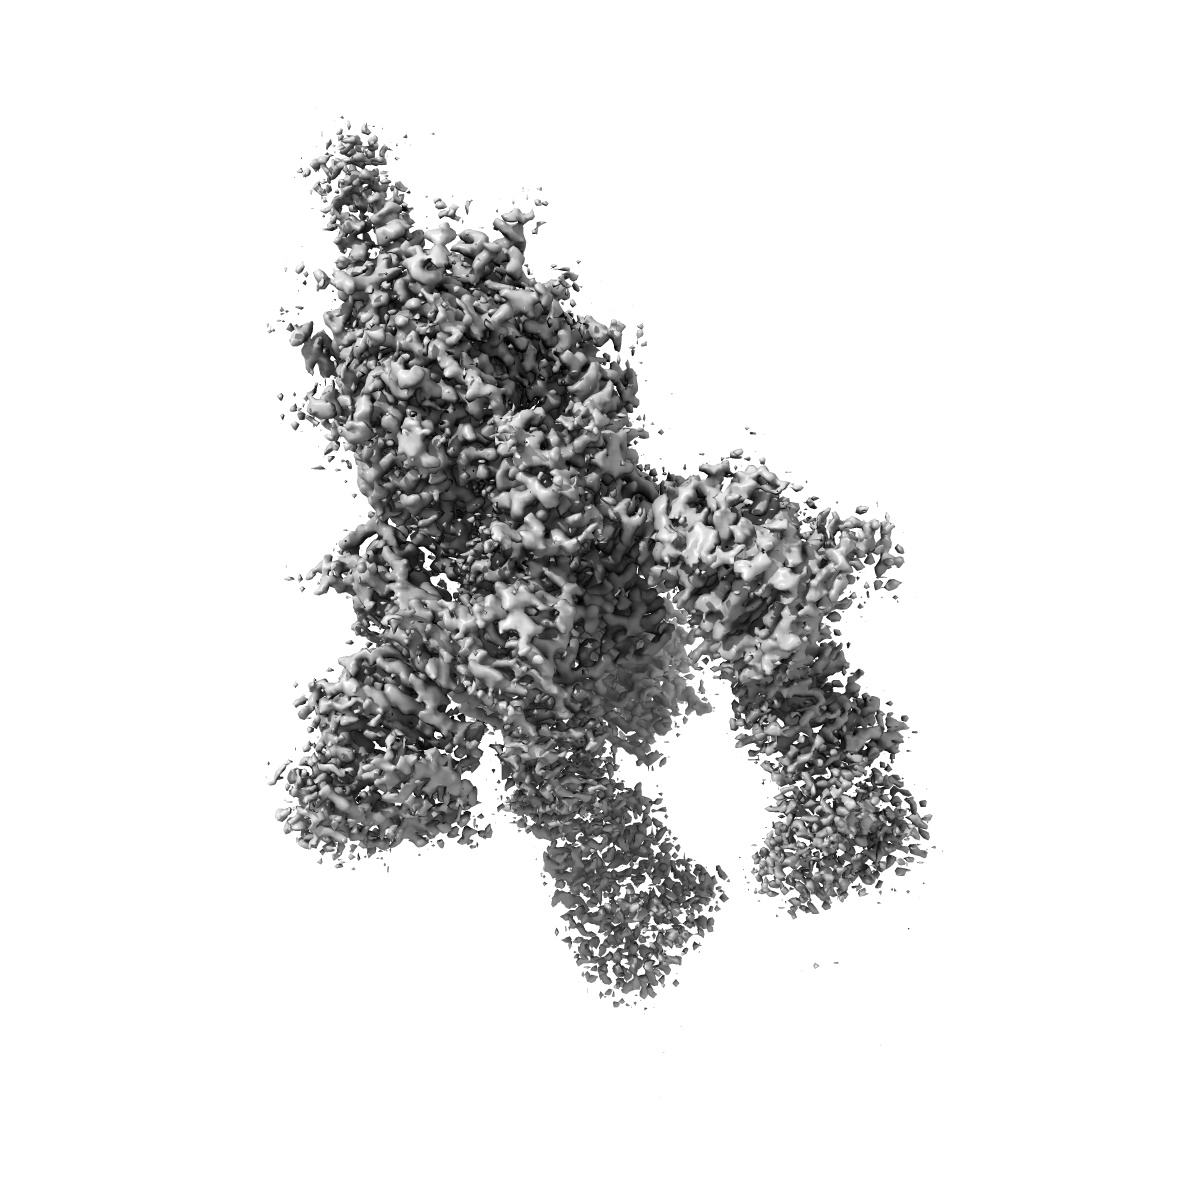

cryo EM map of the S protein of SARS-CoV-2 in complex bound with P2B-1A10

Single-particle2.8 Å

Sample: S protein of SARS-CoV-2 in complex bound with P2B-1A10

Fitted models: 7czq